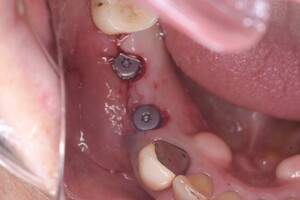

インプラント治療の症例4

口腔内写真

- Befor

- After

| 治療内容 | 左下6番抜歯、左下6番7番骨造成、インプラント埋入 |

| 治療方針 | 元々支台歯に負荷がかかりやすいとされている延長ブリッジを抜歯し、1本単体でしっかりかめるようにインプラントを2本埋入した。骨吸収も進んでいたため、※GBR法で骨造成を同時に行った。 治療と並行して、全顎的な歯周病治療も行い、今後は歯周病が進行しないよう、こまめにメンテナンスに通っていただく。 |

| 担当者所見 | 6番は歯根分割された被せ物が7番の欠損部との延長ブリッジとされており、強い咬合と歯周病も相まって負荷がかかり動揺し、歯として機能しなくなったため、抜歯となった。 |